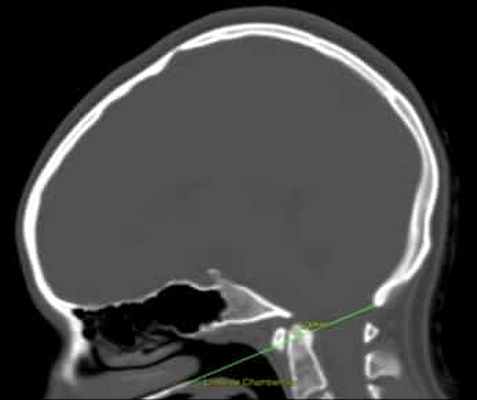

Для диагностики положения зубовидного отростка относительно БЗО традиционно используется оценка трех линий на сагиттальной краниограмме (МРТ, КТ): МакРэя, Чемберлена и МакГрегора.

Линия Чемберлена проводится от твердого неба к Опистиону (точка, расположенная по центру задней части края БЗО. Зубовидный отросток в норме находится ниже этой линии на 1.8мм у мужчин и на 1мм у женщин. Допустимым является, если зубовидный отросток заходит за линию Чемберлена не больше, чем на 2.5 мм (при отсутствии компрессии нервных/сосудистых структур). Диагноз базилярной инвагинации устанавливается в случае нахождения зубовидного отростка на 5 мм выше линии Чемберлена.

Рисунок 1. Базиллярная импрессия. КТ головного мозга с линией Чемберлена, которая соединяет заднюю стенку большого затылочного отверстия с передней стенкой твердого нёба и должна проходить по верхней части атланта. В данном случае атлант превышает границу на 5,3 мм.

Для диагностики и контроля базиллярной импрессии проводится КТ черепа или рентген головы и шейного отдела в боковом плане.

Иногда диагноз ставят по результатам МРТ головного мозга, но затем во время контроля прибегают чаще всего к КТ черепа или рентгену.

Диагноз ставится при помощи измерения линии Чемберлена и/или других показателей (см. Рис.1).